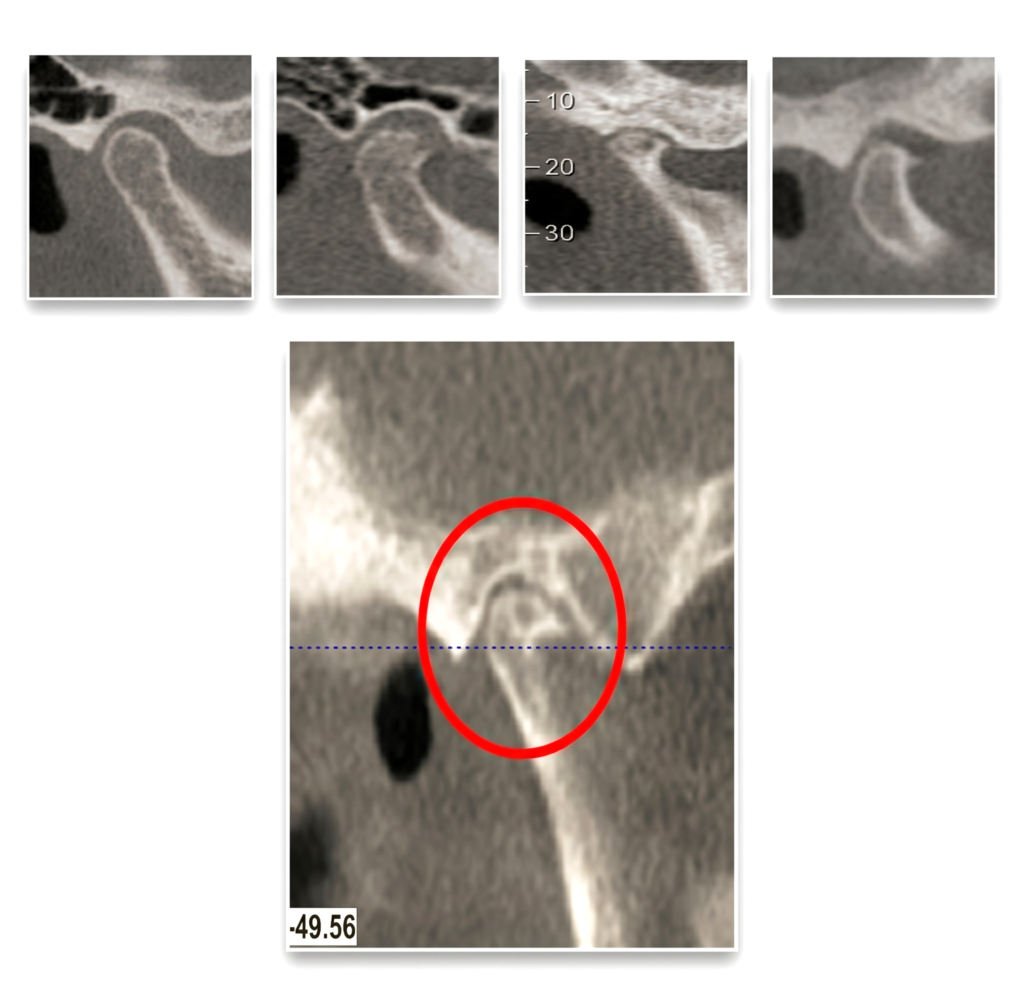

He is certified in Cone Beam Computed Tomography (CBCT) and has extensive experience in advanced radiological diagnosis. Dr. Singh is associated with several reputed centers across India as a consultant radiologist for CBCT reporting. His expertise includes implant planning, impacted teeth localization, oral and maxillofacial pathology interpretation, TMJ assessment, maxillary sinus evaluation, and airway analysis.

Bilateral TMJ (open and close mouth) – 3D Scan 3500/-

Unilateral TMJ (open and close mouth) 1800/-

Bilateral TMJ (open and close mouth) – 2D Radiograph 1000/-